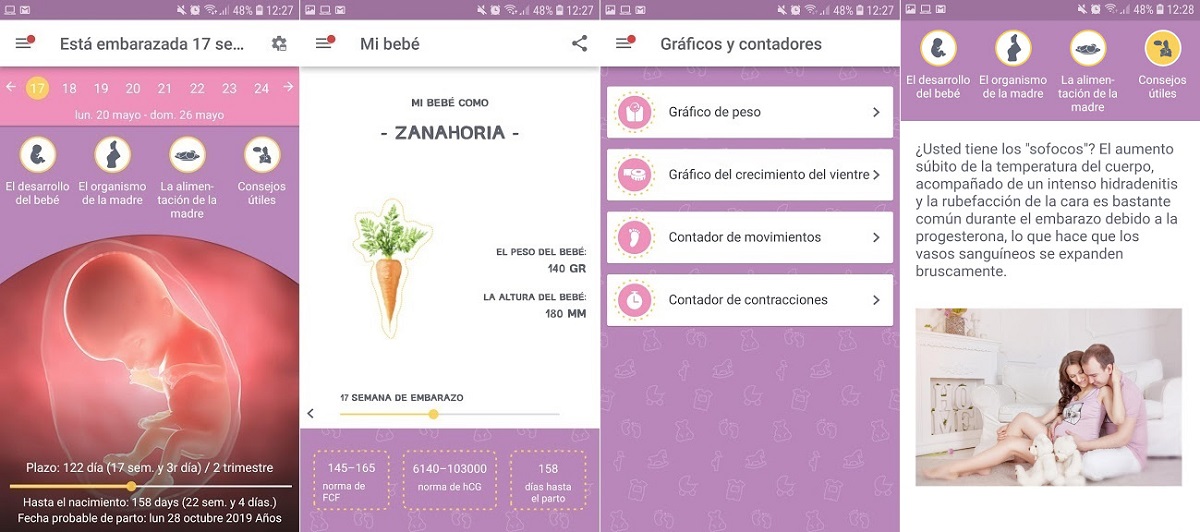

4. Calendario del embarazo

Como ves, hay muchas aplicaciones que pueden ayudarnos a hacer un buen seguimiento del embarazo, con información nutrida y útil. Calendario de embarazo también nos parece una buena aplicación para llevar el control de todo o casi todo lo que necesitas saber durante el embarazo.

La única pega que le pondríamos a la aplicación es que muchos de los textos son traducciones al inglés y que en algunos puntos no están muy bien logradas. Por lo demás, es una buena herramienta que proporciona información fiable y verificada de la Organización Mundial de la Salud (OMS) y la Sociedad Americana de Obstetras-Ginecólogos (ACOG). Podrás informarte sobre el desarrollo del bebé, los cambios en el organismo de la madre, la alimentación y otros consejos útiles.

Se incluye, además, un sistema de gráficos para el peso, el crecimiento del vientre, un contador de movimientos y otro de contracciones, para cuando llegue el momento del parto.